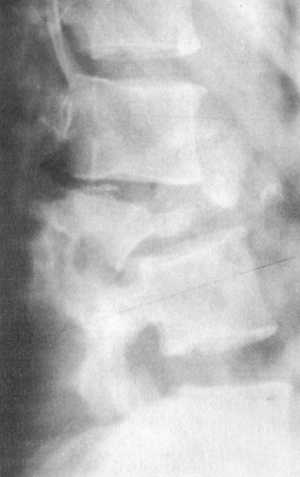

Неврологическая симптоматика маловероятна. При возникновении клиновидной деформации

тела позвонка она может быть несимметричной, что приводит к нарушению оси не

только в сагиттальной, но и во фронтальной плоскостях (рис. 5.2).